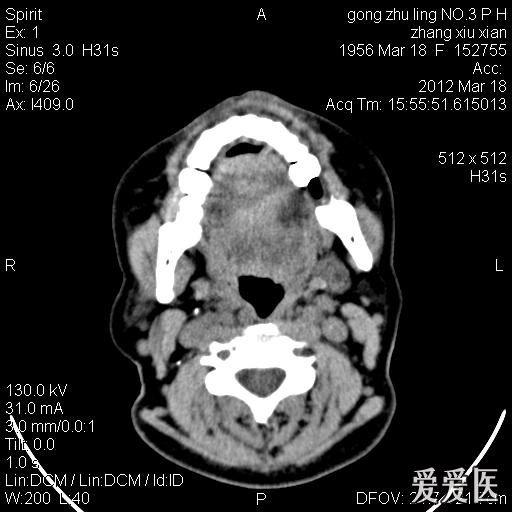

鼻前庭囊肿一例分享!

图片尺寸512x512